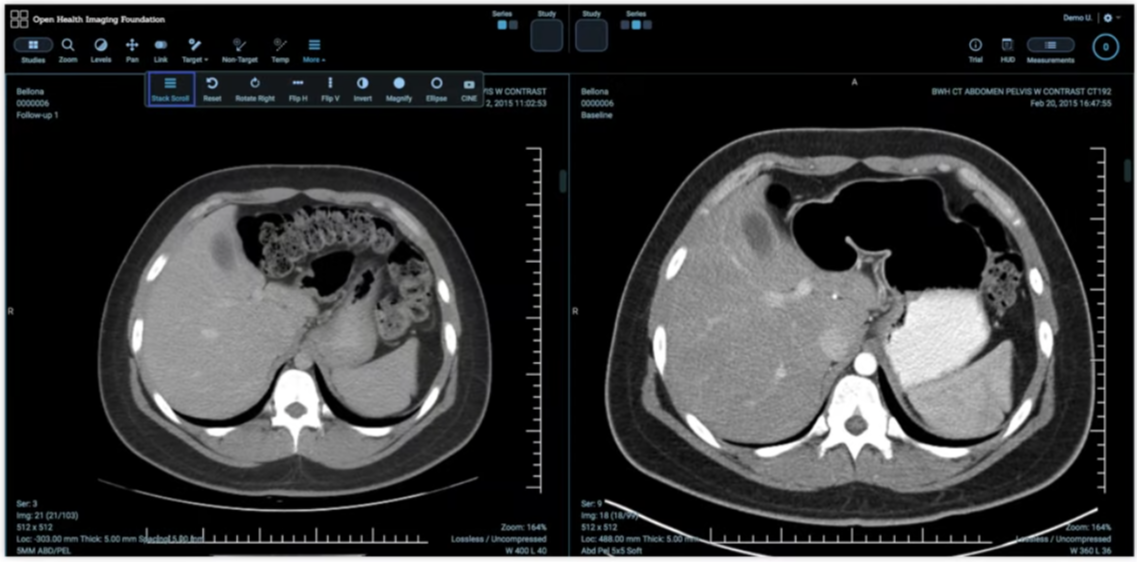

That is why imaging on Google Cloud still revolves around DICOM-aware components. Medical Imaging Suite supports imaging data management, clinical collaboration, and AI-ready workflows, while Cloud Healthcare API DICOM stores and DICOMweb keep standards-aware ingest and retrieval in scope.

Modern imaging viewers and portals work better when image search and retrieval can move through HTTP-native infrastructure. DICOMweb matters because it makes browser-safe access, gateway controls, and API-style integration possible without losing DICOM identity or study hierarchy.

Operationally, this also changes how imaging systems scale. Google documents DICOMweb as the main programmatic access path and pairs it with imaging-specific best practices so applications can separate metadata search, targeted retrieval, and downstream event handling instead of treating the archive like one opaque file share.